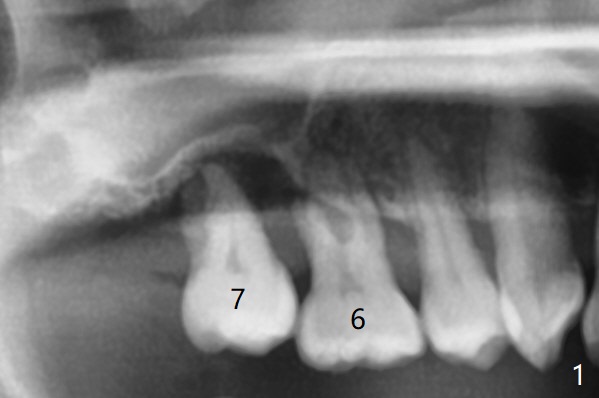

45岁女右上7严重骨质吸收终于开始出现症状(图一),虽然邻牙(6)骨质吸收也明显(图二,四,六,八,十),但是保留它,远中颊侧(DB),腭侧(P)根成为骨粉(图三,五,七,九,十一:红圆圈)支架。